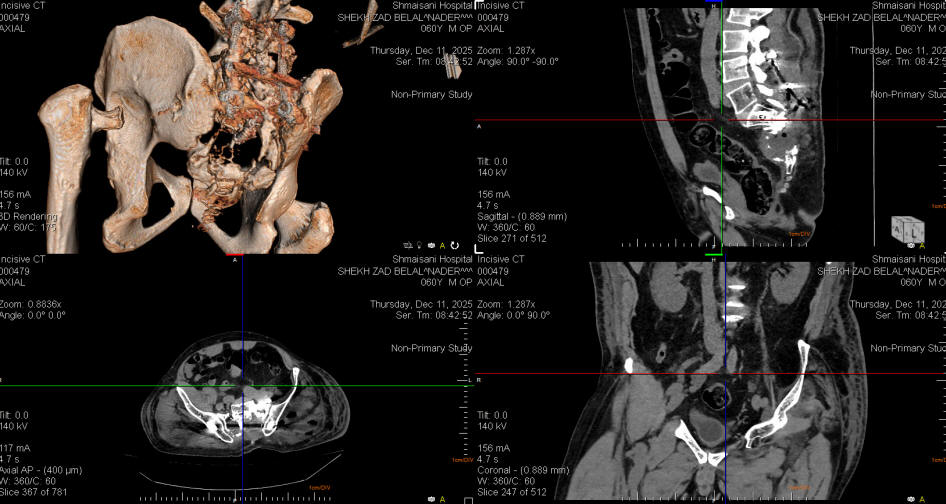

10-DEECEMBER-2025  SHIRZAD BELAL NADER  60 YEARS  REVISION OF THE ILIAC SCREWS AND REDIRECTION.

The patient was operated by me 08-December-2025 for progressing chordoma. The patient neurological status improved, but check CT-scan of the pelvis done the next day with ORS Visual program showed unacceptable direction of the iliac screws, for what he was brought to the operating room to redirect the iliac screws.

The wound was opened and further dissection lateral to sacroiliac joint was accomplished to visually follow the track of the screw to be kept inside the bone. Calculation of the direction of the iliac screws according to ORS Visual software was to put the screws 20 degrees more medial in the saggital plane. The right iliac screw was 70x9.5 mm and to the left 60x9.5 mm in dimensions. Visual control denied any violation of the iliac bone. Inspection of the tumor cavity was filled by hematoma which was removed and the neural structures were swollen. Routine closure of the wound. Smooth postoperative recovery. He was sent to the ward.

Check CT-scan showing unacceptable direction of the iliac screws, which needs 20 degrees more anterior, for what revision screws was planned the next day. Notice the left iliac bone is thin in the left side and severely atrophied the left iliopsoas muscle.

Check CT-scan performed 11-December-2025 with ORS Visual software showing the iliac screws inside the iliac bones.